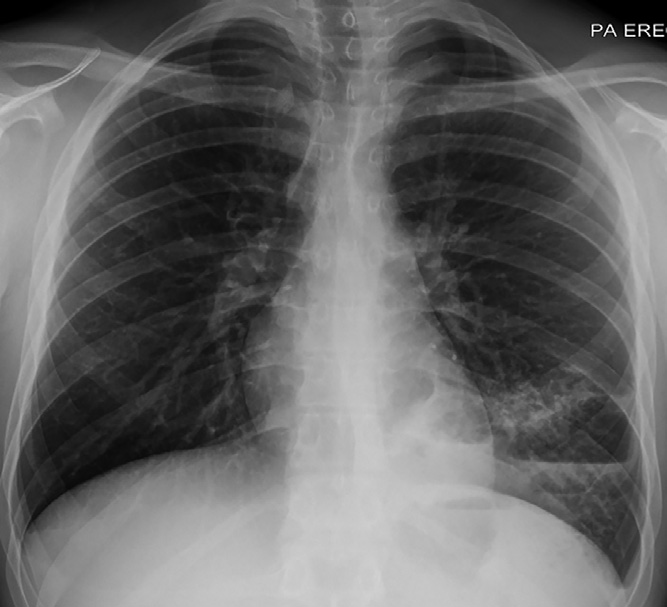

胸內(nèi)結(jié)節(jié)病是一種原因不明的,以非干酪樣壞死性上皮樣細胞肉芽腫為病理特征的系統(tǒng)性疾病。而肺結(jié)核則是由結(jié)核分枝桿菌導致的慢性呼吸道傳染病。兩者病理上均可表現(xiàn)為上皮樣細胞肉芽腫,且臨床表現(xiàn)具有一定的相似性,容易造成誤診和誤治。近日,《結(jié)核病流行背景下胸內(nèi)結(jié)節(jié)病與結(jié)核病臨床鑒別與處置專家共識》于《中國防癆雜志》發(fā)布,該共識從臨床表現(xiàn)、影像學特征、支氣管鏡檢查、病理學診斷與病原學檢查等多方面對兩種疾病的鑒別進行分類闡述,以下為共識要點。

推薦意見2:應采用高分辨率CT和增強CT對胸內(nèi)病變進行系統(tǒng)評價,并結(jié)合動態(tài)CT隨訪提出傾向性診斷。(表1為評估結(jié)節(jié)病與結(jié)核病影像診斷分級中幾種不確定征象時的診斷傾向提示)